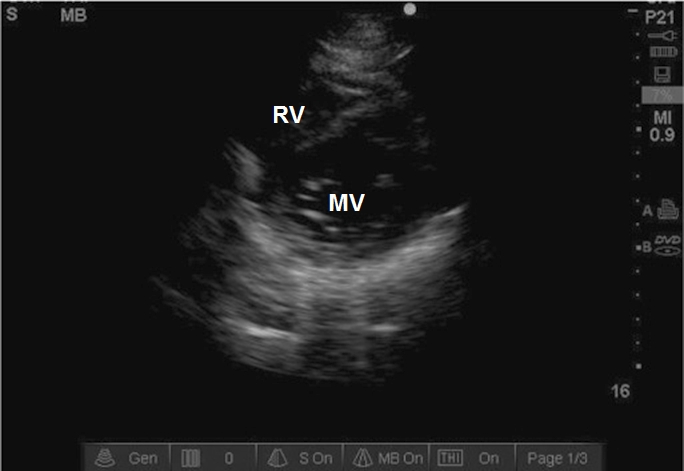

Case 7-8. Parasternal Short-axis View at Mitral Valve Level

Video 7-8A. The main utility of this study is to assess segmental wall function of the basal segments, which are normal in this case. MV function may be observed as well, although other views may be more helpful.

Video 7-8B. Severely reduced left ventricular (LV) function without segmental wall abnormality (acknowledging the poor basal anterior and basal anterolateral wall visualization). In conjunction with the reduced LV function, there is reduced opening of the MV.

Video 7-8C. This video demonstrates a less common cause of reduced MV opening related to mitral stenosis. Planimetry of the MV opening is one method of measuring the severity of MS, although it requires attention to gain, angle, and cross section; Doppler based methods should also be utilized.